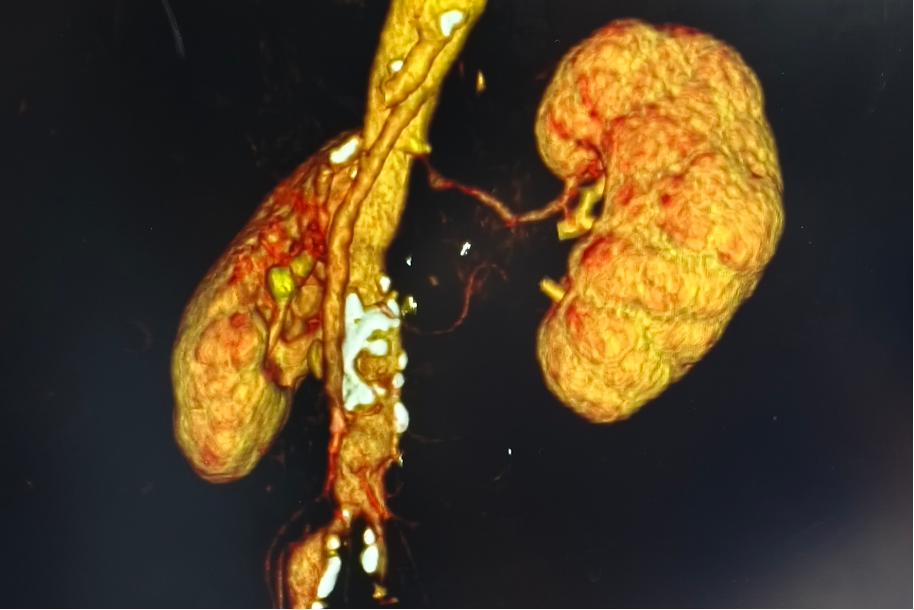

(术前CTA)

为明确诊断,进一步为患者完善肾动脉CTA检查,结果证实其左侧肾动脉管腔重度狭窄,确诊为继发性高血压。心血管科全体医师经病例讨论一致认为,唯有通过介入手术解除肾动脉狭窄,才能从根本上解决问题。术前积极评估肾动脉介入入路情况,考虑该患者左侧髂内动脉血栓不排除,左侧入路困难;如患者右侧髂动脉狭窄、钙化或走行迂曲,则手术难度显著增加。为了进一步了解入路情况,完善了盆腔CTA检查,结果提示左侧髂总动脉重度狭窄,右侧髂总动脉轻度狭窄。